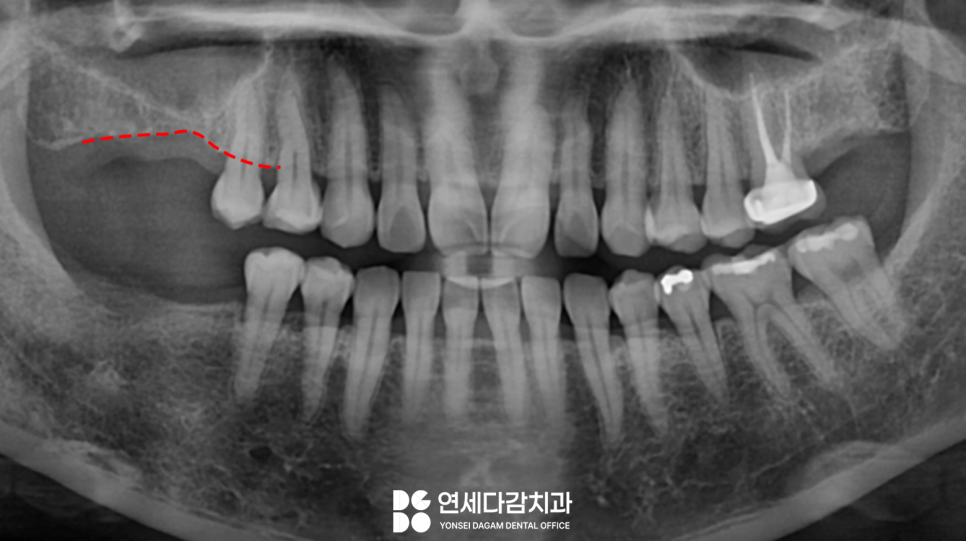

오른쪽 위아래 어금니 부위에

이가 결손된 채로 방치하고 있다가

임플란트를 진행하게 된 케이스입니다.

오랜 기간 방치된 탓에

자극을 받지 못한 잇몸뼈가 흡수되어

움푹 들어간 모습을 확인할 수 있습니다.

정확한 진단을 위해 CT를

촬영하여 확인해 본 결과,

상악동의 함기화를

발견되었습니다.